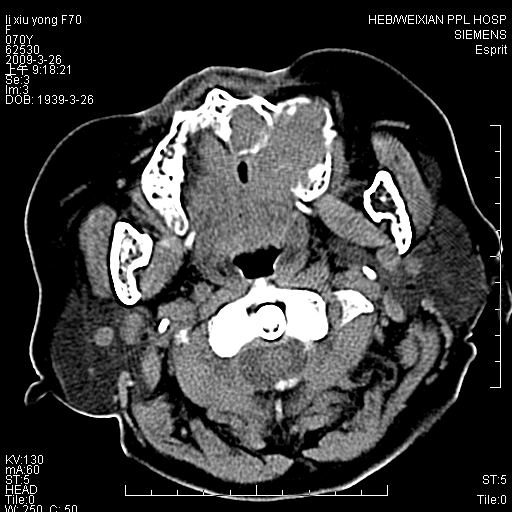

标题: CT19708:单侧上颌窦病变

老年患者,女。鼻塞多年。

考虑右侧上颌窦良性占位性病变,粘液囊肿可能性大;建议活检。

膨胀性生长,且骨质无破坏,说明时间久,良性;从密度,边缘看,内部还见坏死区,应该是实性肿瘤,定性,影像学无绝对的特异性

病灶密度很不均匀,骨壁膨胀中有断裂,考虑内翻乳头状瘤可能性大,粘液囊肿不排除

膨胀性生长,且骨质无破坏,说明时间久,良性;从密度,边缘看,内部还见坏死区,应该是实性肿瘤,定性,影像学无绝对的特异性,考虑内翻性乳头状瘤可能